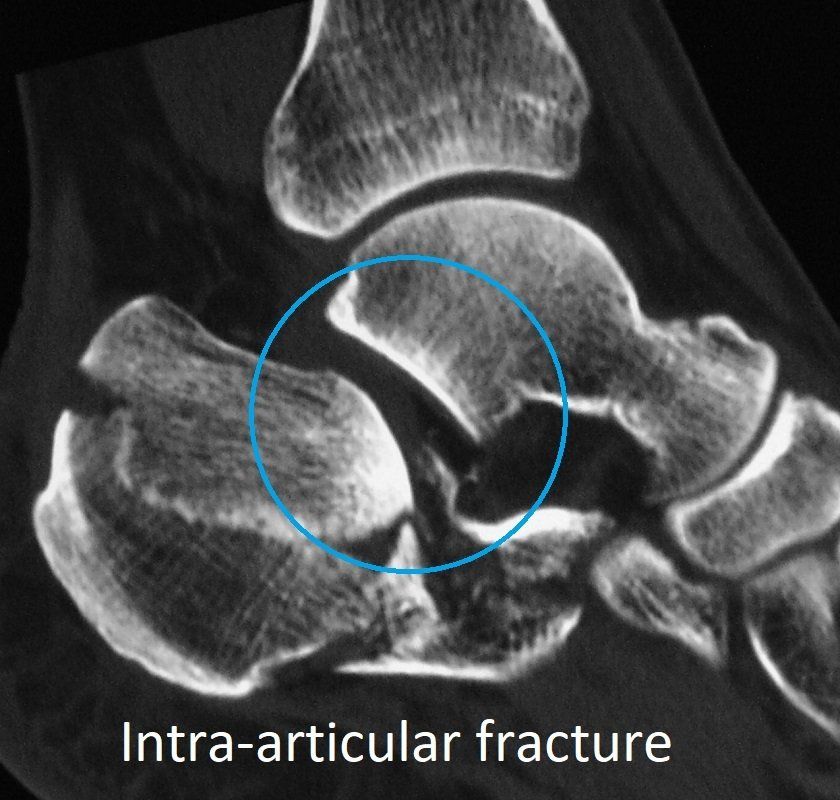

- This crushes the calcaneus making it spread out sideways and lose height.

- Injury to the subtalar joint is common (intra-articular fracture).

- X-rays

- CT scan.

These imaging investigations show which part of the calcaneus is broken, and how badly. This determines both the need for surgery and the risk of long-term complications. Severe injuries can lead to hindfoot osteo-arthritis.